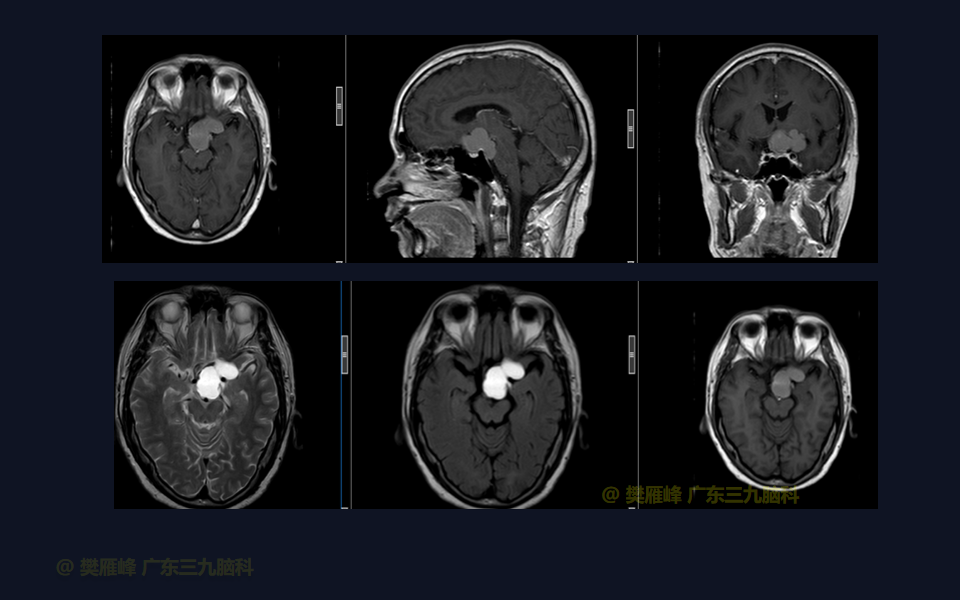

在这个二维手术视频中,展示了一种经翼点入路颅咽管瘤。患者是一名50岁的男性,有1月的左眼视物模糊、无多饮多尿病史,神经影像学显示鞍上区-桥前池示一团块状短T1长T2,Flair序列高信号,分叶状,边缘轻度线样强化,大小约47.5×33×33mm,邻近左侧颈内动脉-大脑前、中动脉局部受包绕的鞍上的颅咽管瘤。经术前讨论选择经扩大翼点入路颅咽管瘤切除,以实现肿瘤全切除,保护周围神经血管。术后术后尿量增多,10天后好转;视力、视野同术前改变;神经影像学显示肿瘤全部切除。我们展示了安全的神经血管保护和肿瘤切除术的细微差别和技术要点,以及手术技术。